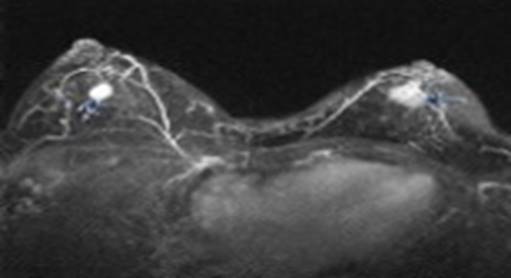

磁共振设备适用于肌肉、肌腱、韧带、脂肪等软组织成像,在神经系统疾病、心血管疾病等方面有明显优势。 磁共振的发展: